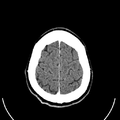

تصوير مقطعي حاسوبي

التصوير المَقْطَعي الحاسوبيX-ray computed tomography نظام تصوير بالأشعة السينية، يُسْتخدم لتصوير مختلف أجزاء الجسم مثل الرأس والقلب والبطن. ويستعين الأطباء بالتصوير المقطعي الحاسوبي على تشخيص الأمراض وعلاجها. وتسمى هذه التقنية أيضًا التصوير المقطعي المحوسب أو التصوير المقطعي المحوري المحوسب.

ويستعمل الأطباء فحوص التصوير المقطعي الحاسوبي لتشخيص كثير من الحالات مثل الأورام والإصابات وتجلطات الدم وكسور العظام. ويساعد التصوير المقطعي الحاسوبي أيضًا في معالجة بعض الأمراض، التي قد تتطلب جراحة بطريقة أخرى. فمثلا،ً يمكن للأطباء استعمال التصوير المقطعي الحاسوبي لإرشادهم إلى إدخال القثطار (أنبوب رفيع) إلى خُرّآج في الجسم لسحب الصديد من المنطقة الملوثّة.

معرض الصور